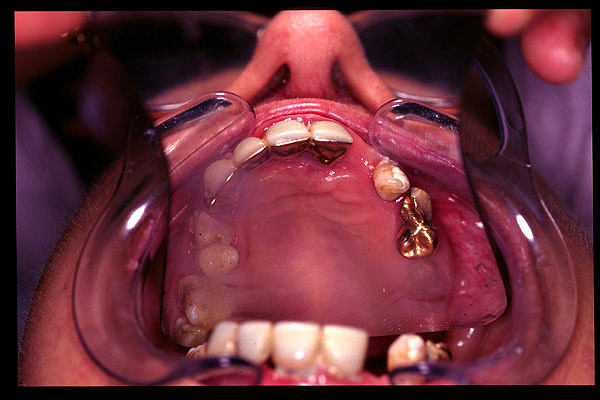

CM Esquelético superior